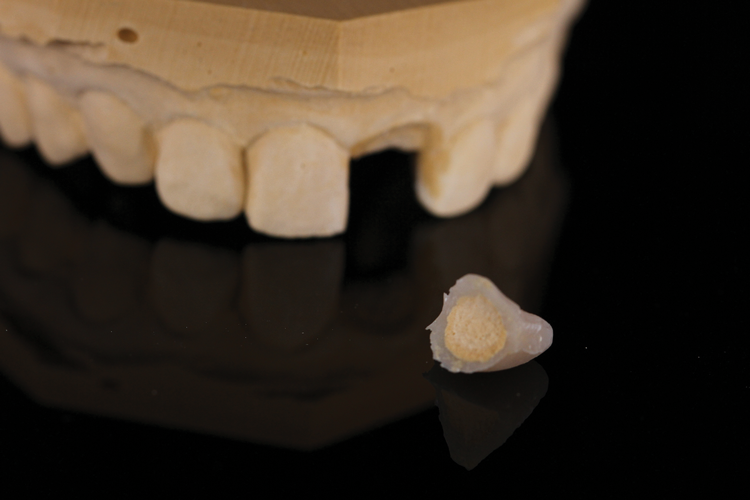

(9.) Intaglio and facial views of the cleaned and polished composite shell, which is ready for conversion into the provisional restoration.

Figure 9

(10.) Intaglio and facial views of the cleaned and polished composite shell, which is ready for conversion into the provisional restoration.

Figure 10